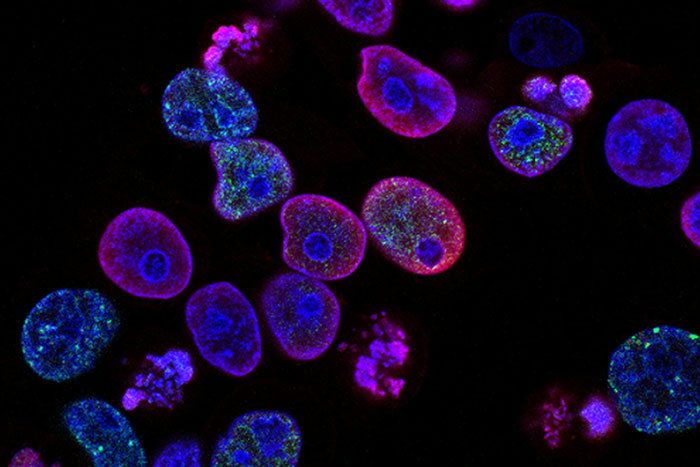

#10

The truth about HeLa cells. These cells grow and divide constantly and are used in all sorts of medical research to discover cures for cancer and other diseases. They were originally harvested from a woman named Henrietta Lacks who had cervical cancer that was fatal. She died in 1951. Her family didn’t know that her cells were even being used until recently. These cells were basically stolen from Henrietta by a doctor and he made millions from them, and Henrietta’s family never knew. Once they found out, they finally settled with a biotech company for an undisclosed amount. This woman has basically saved so many of us, and we all owe her so much.

Image credits: KweenBee1986